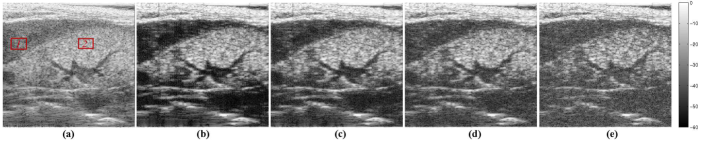

In this section, we tested our method with two in vivo data sets. The experimental data were acquired with a 20 MHz single-element US probe on a mouse bladder (first example) and kidney (second example). Unlike the simulated cases studied previously, the PSF is not known in these experiments and has to be estimated from the data. In this paper, the PSF estimation method presented in [35] has been adopted. The PSF estimation adopted is not iterative and the computational time for this pre-processing step is negligible compared to the reconstruction process. The compressive deconvolution results are shown in Figures 5 and 6 for different CS ratios.

where μ1subscript𝜇1\mu_{1} and μ2subscript𝜇2\mu_{2} are the mean of pixels located in two regions extracted from the image while σ1subscript𝜎1\sigma_{1} and σ2subscript𝜎2\sigma_{2} are the standard deviations of the same blocks. The two regions selected for the computation of the CNR are highlighted by the two red rectangles in Figures 5(a) and 6(a). Table. III gives the CNR assessment for these two in vivo data sets with different CS ratios and p𝑝p values. Given the sparse appearance of the bladder image in Fig. 5(a), the best result was obtained for p𝑝p equal to 111. However, the complexity of the tissue structures in the kidney image in Fig. 6 results into better results for p𝑝p larger than 111. Nevertheless, both the visual impression and the CNR results show the ability of our method to both recover the image from compressive measurements and to improve its contrast compared to the standard US image. In particular, we may remark the improved contrast of the structures inside the kidney on our reconstructed images compared to the original one.

Refer to caption

Figure 5: From left to right, the original in vivo image and its compressive deconvolution results for CS ratios of 1, 0.8, 0.6 and 0.4 respectively with p=1𝑝1p=1.

Figure 6: From left to right, the original in vivo image and its compressive deconvolution results for CS ratios of 1, 0.8, 0.6 and 0.4 respectively with p=1.5𝑝1.5p=1.5.

TABLE III: CNR assessment for in vivo data

Figure Original CNR p𝑝p values CS ratios

100% 80% 60% 40%

Fig.6 1.106 p = 1 1.748 1.546 1.367 1.333

p = 1.5 1.690 1.424 1.304 1.287

Fig.7 1.316 p = 1 2.373 2.162 1.895 1.434

p = 1.5 2.317 2.082 1.905 1.451